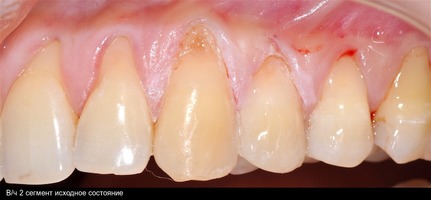

В марте 2017 года в клинику обратилась пациентка Ч., 28 лет (табл. 1) без вредных привычек, с положительным социальным статусом, астенического телосложения. С жалобами на тотальное обнажение корней зубов с повышением чувствительности от термических раздражителей, эстетические дефекты, абразии твердых тканей зубов.

Исходный объем мягкотканного комплекса атрофичен, тонкий биотип десны. Мелкое преддверие полости рта на нижней челюсти в переднем отделе, от 44-го до 34-го зубов высокое прикрепление слизисто-мышечных тяжей.

Форма зубной дуги — эллипсовидная, с незначительным сужением в области премоляров на верхней челюсти; во фронтальных участках верхней и нижней челюстей окклюзия в протруссии. Зубы крупные, вытянутые по форме. Межальвеолярный контакт в норме, прикус ортогнатический. Гигиенические индексы: IG–1,2(HYG),PI—6,GI—0,PBI—0.

В области от 1.6 до 2.6 и от 3.6 до 4.6 все зубы имеют некариозные поражения разной степени, такие как эрозии эмали и клиновидные дефекты, вовлекающие в процесс ткани эмали и дентина. Подвижности зубов не выявлено (рис. 1а-е) [9].